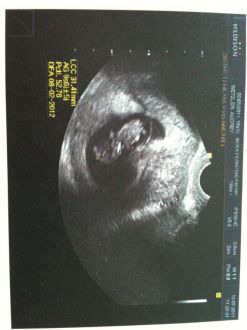

2e échographie

12 Juillet 2011 :

Enceinte de 8 SG, encore trop tôt pour l'échographie du 1er trimestre!

Mais enfin nous avons pu voir notre petit amour et entendre son cœur!! Quel moment d'émotion, lorsque j'ai entendu son petit cœur battre c'était magnifique et ça concrétisait vraiment qu'il y avait un petit être qui se développe en moi!!!! Il mesure 31.41 mm!!

Message déposé le 16.08.2011 à 09:45 - Commentaires (0)